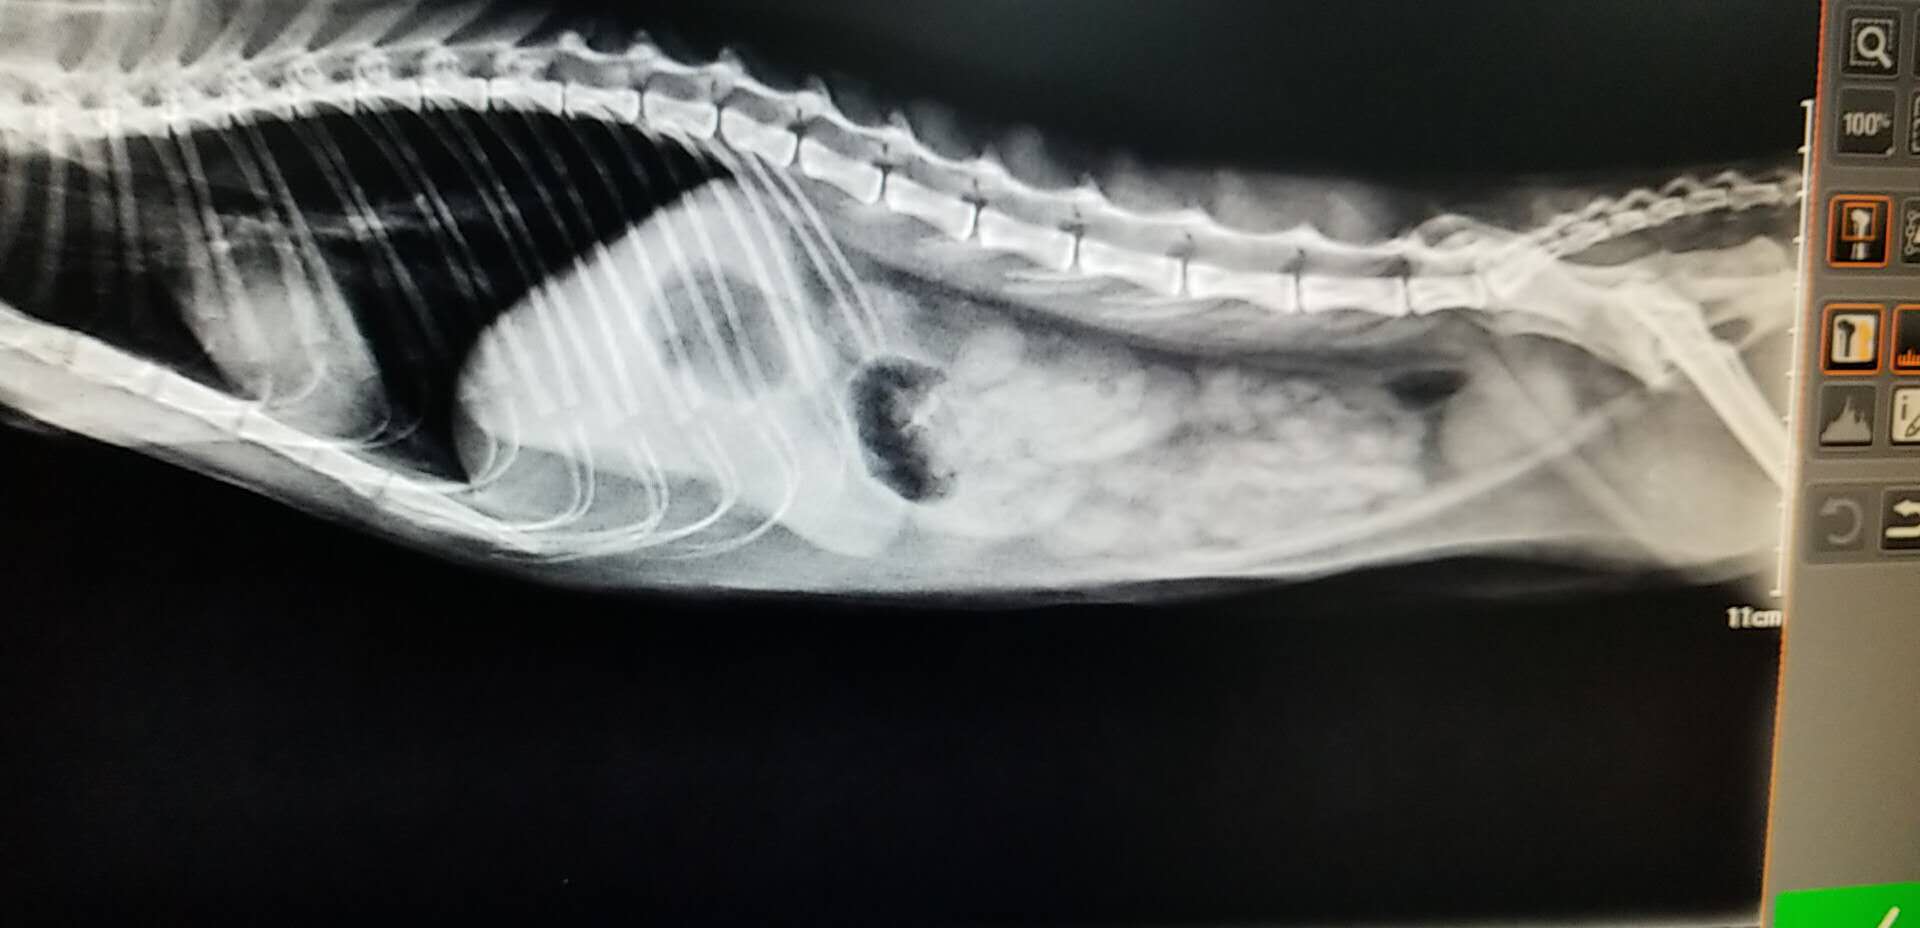

★血液以及影像学检查:血常规提示患猫存在轻度的脱水,生化检查未见明显异常。X-ray提示腹腔存在少量气体,肠腔未见明显异常增大。超声下,可见胃内存在大量的液体,肠腔大量液体,肠道不蠕动,在停止蠕动的肠道段前后扫查,未见明显的异物和肿块。

X-RAY

猫咪的肠梗阻诊断是需要结合生活史,病史,免疫史以及临床的检查(主要是影像学)相结合,进行一步步的排查才可以进行诊断的。X-RAY的检查可见肠管的扩张,会具有特征性的气体影像。站立位置,可见液体和气体间的水平线,阻塞部位下的肠管则是空虚的影像。肠道积液,肠道蠕动异常。血检主要是看患猫是否存在脱水以及长时间的肠梗阻有没有造成严重的并发症,例如:败血症等等。